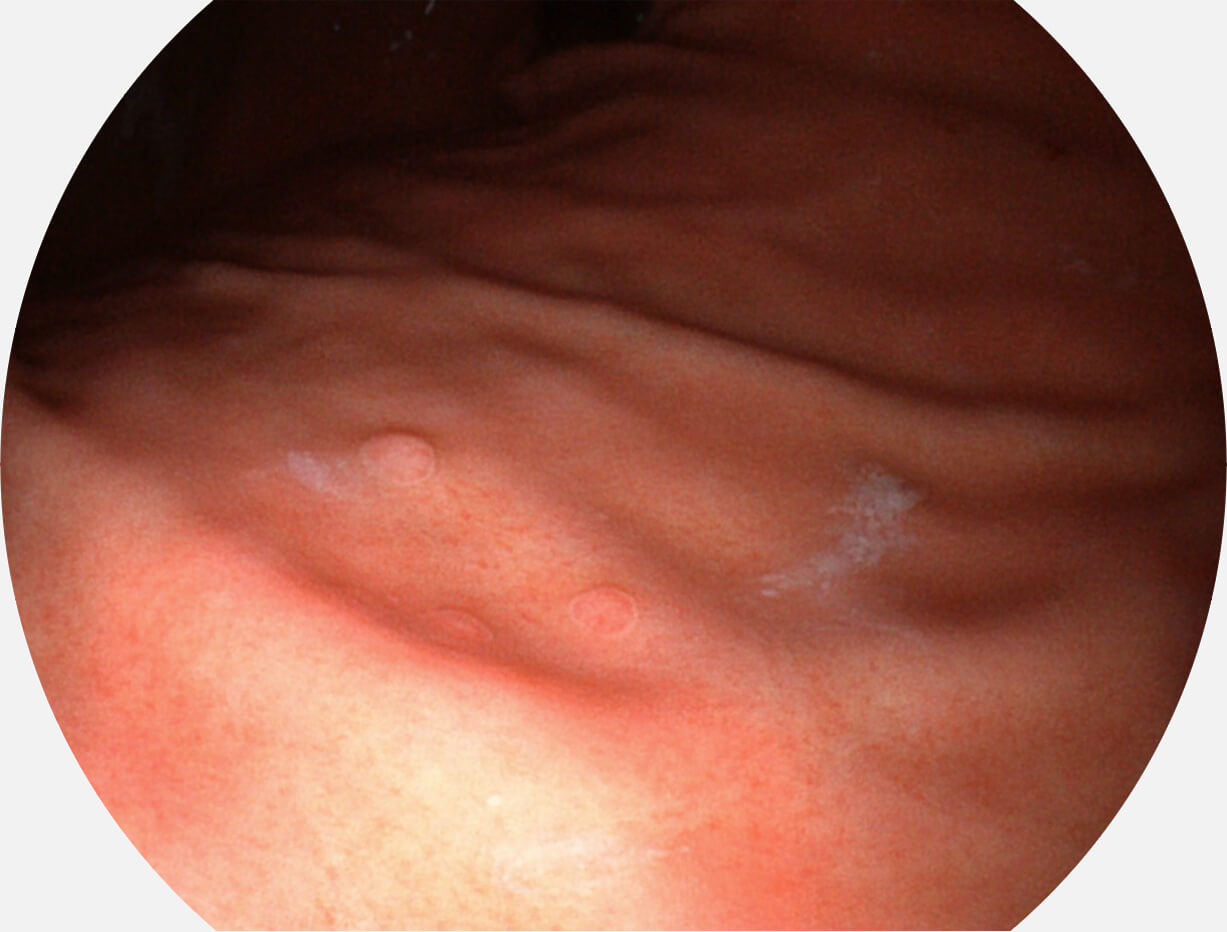

白光图像

图像具有高亮度、高黏膜血管颜色对比度的特点,且不改变粘液、食物残渣、粪便的基本颜色,可在中远景下进行观察,助力消化道早期疾病的诊断。